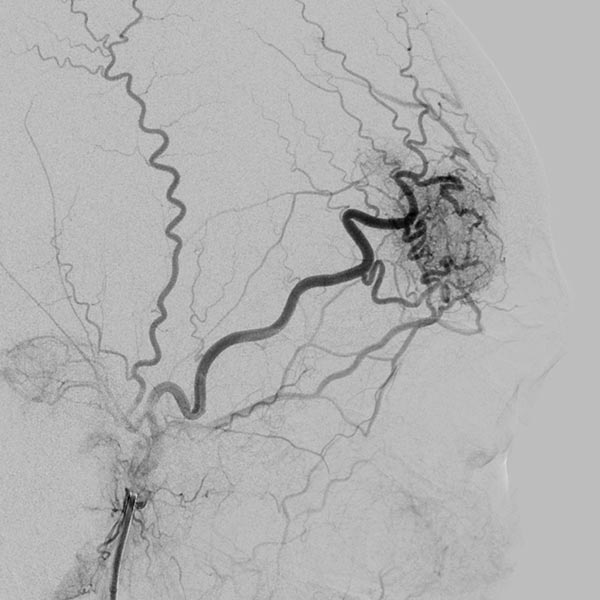

After super-selective catheterization via a microcatheter, stepwise filling of the entire nidus of the AVM using ethylene-vinyl alcohol copolymer with plug-and-push technique, in which the catheter tip is glued in place and the embolic agent is pressed into the lesion. Image in roadmap technique shows previously injected embolic agent in white and newly injected embolic agent in black. Note the increasing retrograde filling of the small feeder artery at the bottom of the lesion (start of injection).

Note the increasing retrograde filling of the small feeder artery at the inferior border of the lesion (during injection).

Note the increasing retrograde filling of the small feeder artery at the bottom of the lesion (after injection). The small artery was retrogradely filled against its flow direction.